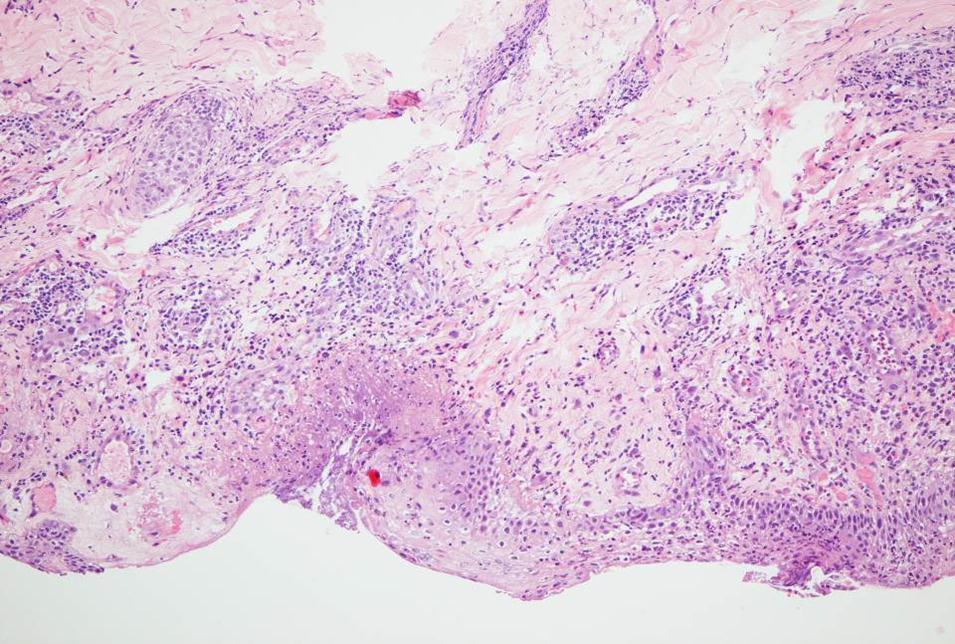

In contrast to IQM alone, the combined use of the fractionated erbium:YAG laser microporation with IQM dominantly induced stronger skin erythema levels starting from visit V2 throughout the last visit V20 (Figure 3a). For the stronger therapeutic responses of crusting and erosions this phenomenon was even more pronounced. By looking at the mean crusting PGA values of V2, V4 and V7 together as early time point of the therapy, arm 2-4 presented with the scores of 0.76±0.3, 1.25±0.2 and 1.3±0.5 compared to the much less pronounced value of crusting in the single IQM control arm-1 with 0.3±0.2. The same is true for the late therapy time point V9/11/13/20 with crusting 2.25±0.8, 2.5±0.5 and 2.3±0.4 arms 2-4 and only 1.3±0.6 in the control arm. For erosions the following mean PGA scores were delineated: V2/4/7 arm 1-4 0.08±0.1, 0.6±0.3, 0.75±0.2, 0.95±0.5 and V9/11/13/20 arm 1-4: 0.5±0.25, 1.2±0.6, 1.37±0.3, 1.44±0.4. Regarding the IQM skin responses no correlation could be found with the amount of shots and pulses used by the laser device. Histopathology of V20 lesional punch biopsies showed in all BCC a dense infiltrate of inflammatory cells which is typical for an adequate IQM response. When this infiltrate was fully replacing signs of BCC the lesions were defined as fully cleared (Figure 4). Within arm 2-4 BCC lesions cleared at 33% (persistent 1 nodular and 1 superficial BCC), 100% and 100% at V20, respectively. Taken together IQM alone led to clearence of 3 out of 4 (75%, persistent a superficial) BCC, though the treatment period was shortened from 6 to 3 weeks. The combined fractionated erbium:YAG laser and IQM application resulted in a slightly better clearance rate of 14 BCC vs. 4 (78%). Notably, those 2 BCC patients, where the laser and IQM application was stopped at V11 also showed full clearence. Figure 5 presents the typical treatment course of a patient in arm 3. Tolerability of the laser microporation was excellent with slight burning or the feeling of small needle sticks during the application. In addition, microporation did not cause any immediate irritation of the skin. Even when erythematous, crusted or eroded IQM lesions were microporated the good tolerability stayed the same. No severe adverse or adverse reactions were noted.

Figure 4.Histopathology of a laser and imiquimod treated basal cell carcinoma at the end of the study (day 20).Focal epidermal necrosis with moderate granulocytic demarcation and reactive perivascular lymphocytic and eosinophilic infiltrates. No residual neoplastic proliferates (HE, x200).